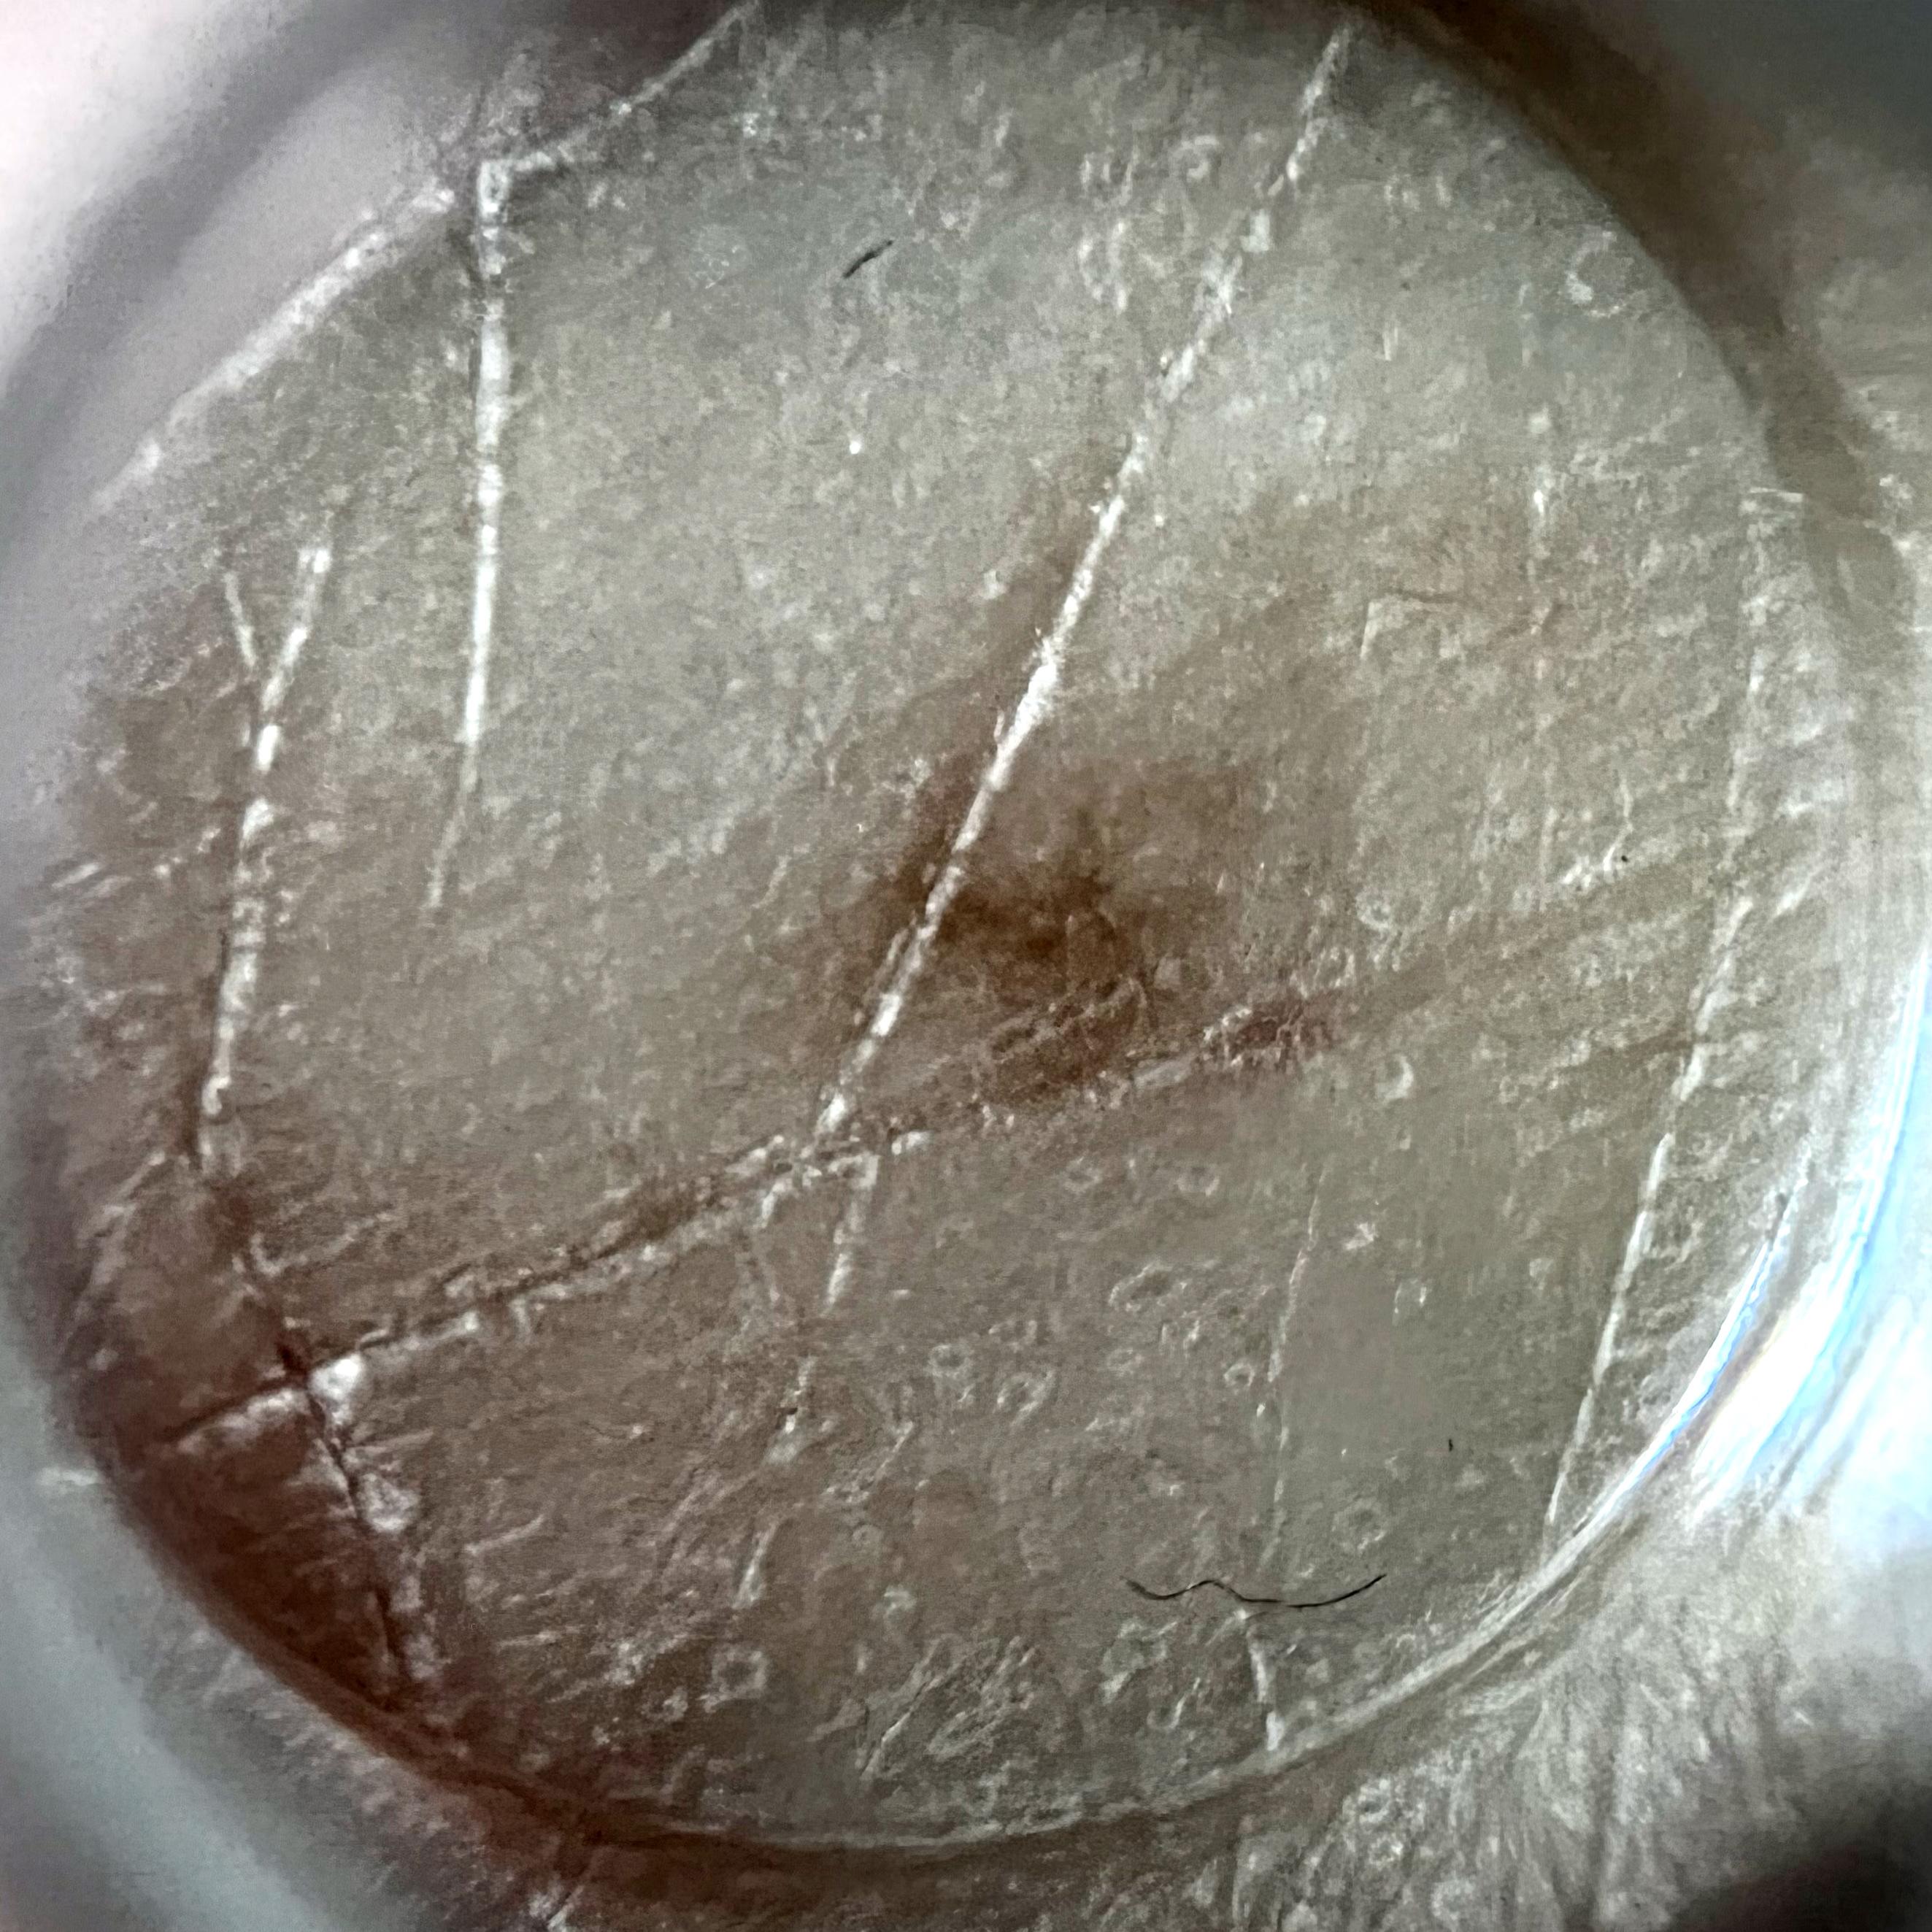

ISIC_7213120

Clinical

Field Value

acquisition_day 277

age_approx 70

anatom_site_1 Lower extremity

anatom_site_general lower extremity

diagnosis_1 Benign

family_hx_mm True

fitzpatrick_skin_type I

image_manipulation instrument only

image_type dermoscopic

lesion_id IL_3605610

patient_id IP_0257923

personal_hx_mm True

sex female